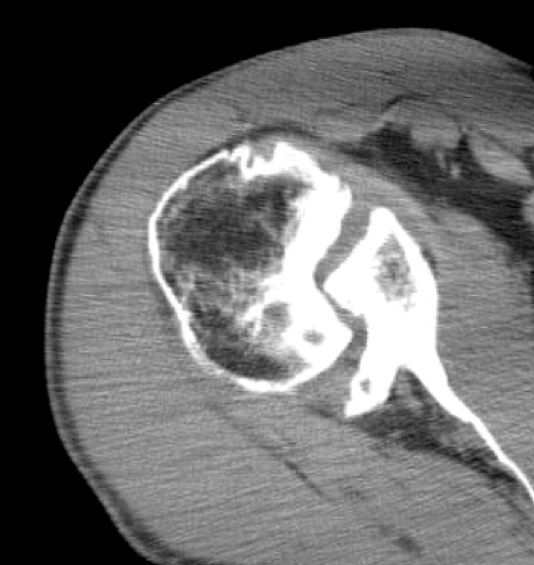

Reverse shoulder replacement the right choice for many patients